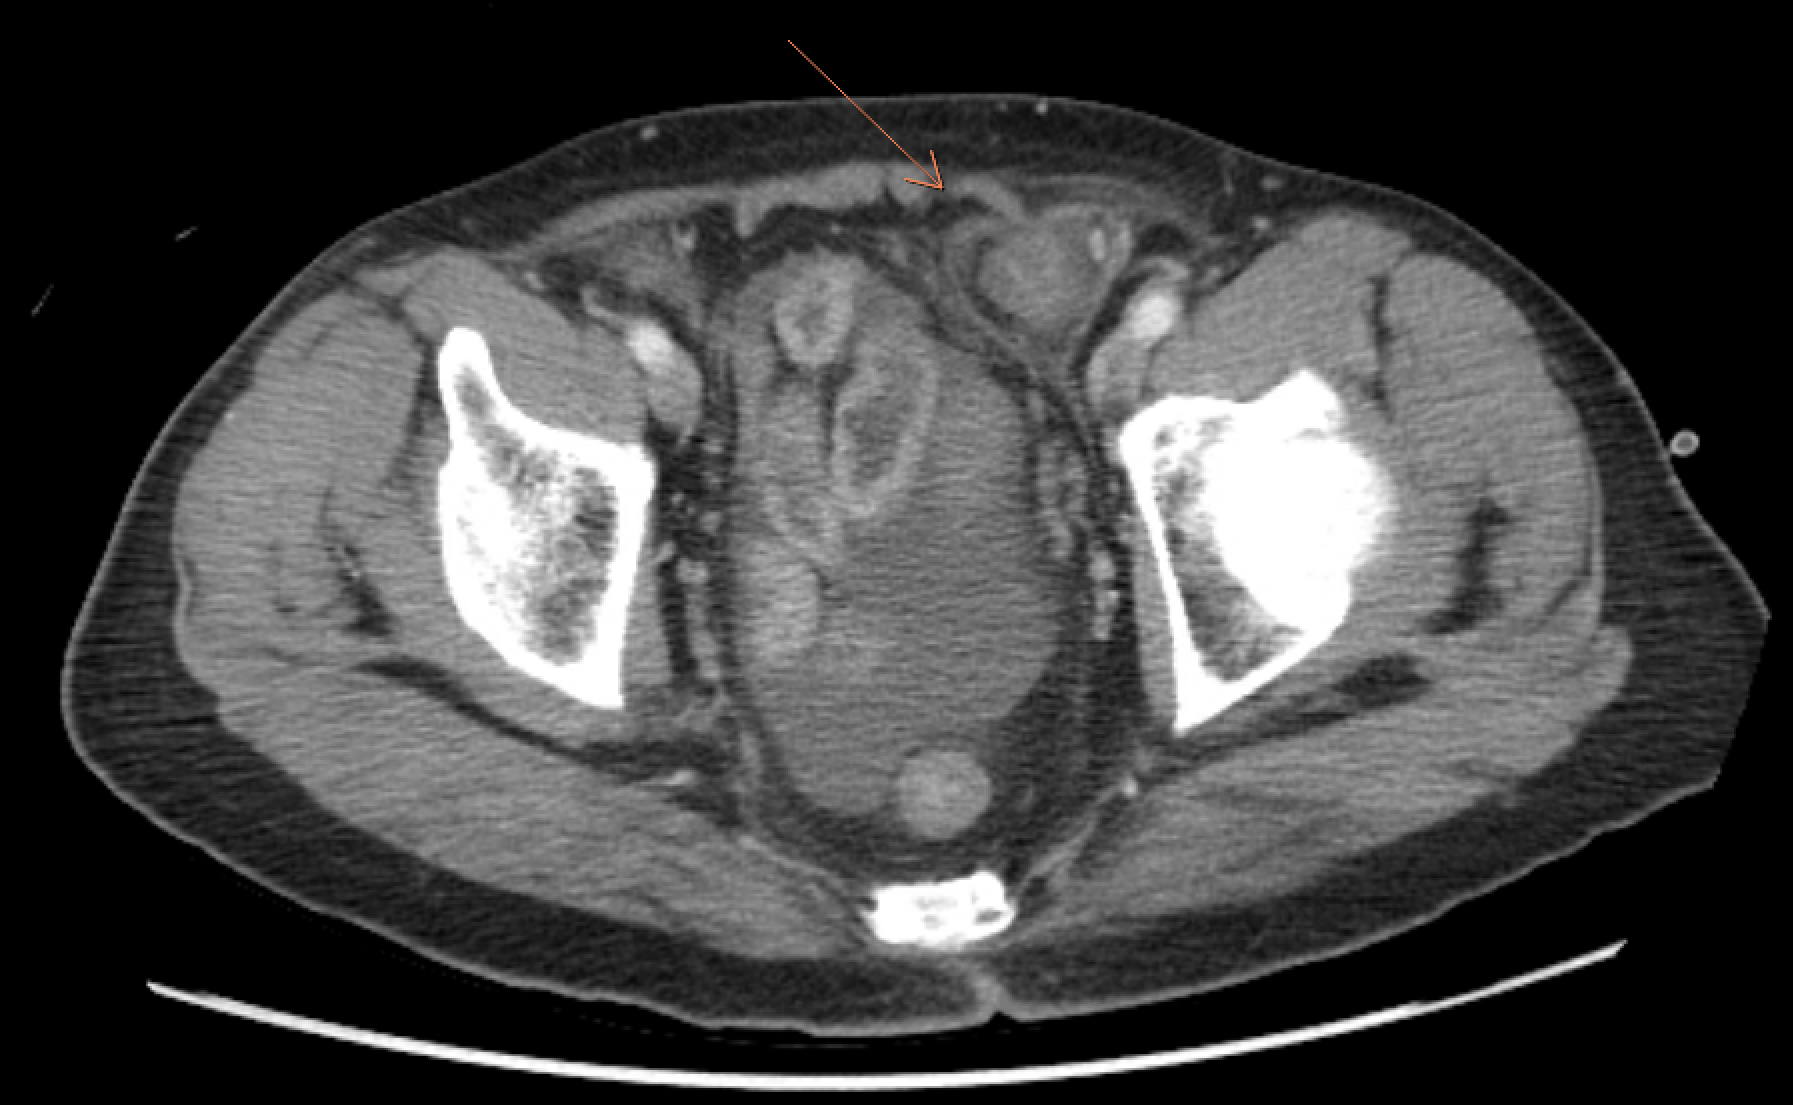

CT Findings: There are dilated small bowel loops involving the jejunum and proximal ileum. At left lower abdomen there is abrupt transition point at ileum with rest of ileal segment distal to transition point being non dilated suggesting mechanical small bowel obstruction. Large bowel is collapsed.

This transition point is closely related to left inguinal hernia, with hernia sac migrated into properitoneal space over left lower abdomen, associated with increased fat stranding,focal bowel mural thickening and adjacent fluid which could suggest incarceration or strangulation. A fibrous constriction band is also noted around the neck of the migrated hernia sac. Under such clinical context of recently reduced inguinal hernia, findings are suggestive of reduction en masse of left inguinal hernia, complicated with SBIO (Small bowel intestinal obstruction).

CT scan typically shows a fibrous constriction band at the neck of the hernial sac in the properitoneal space above the inguinal region. Prompt surgical intervention is necessary to prevent adverse outcomes, especially in cases where there is a delay from symptom onset to surgery.